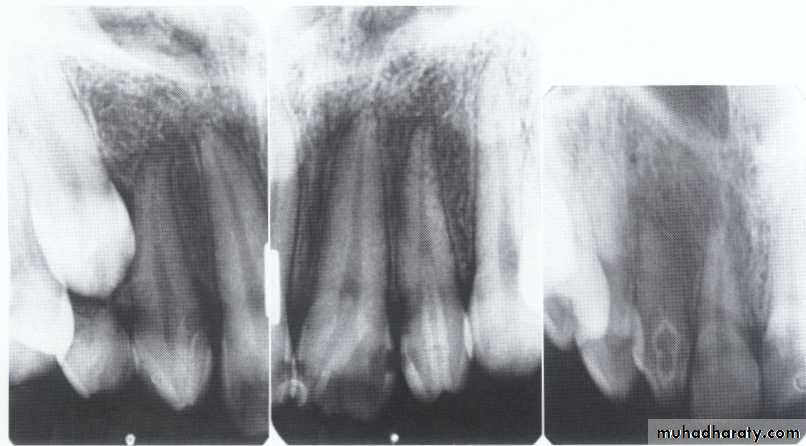

Type I (Radicular Type)

Dentin dysplasia, type I. panoramic & periapical films of the same case show the short and poorly developed roots, obliterated pulp chambers and root canals, and periapical inflammatory lesions.

Type II (Coronal Type)

Dentin dysplasia, type II. panoramic &periapical films of the same case show obliteration of the pulp chamber, reduction in the caliber of root canals, and pulp stones obscuring the flame-shaped pulp chambers.

Periapical inflammatory lesions are associated with some of the mandibular anterior teeth.